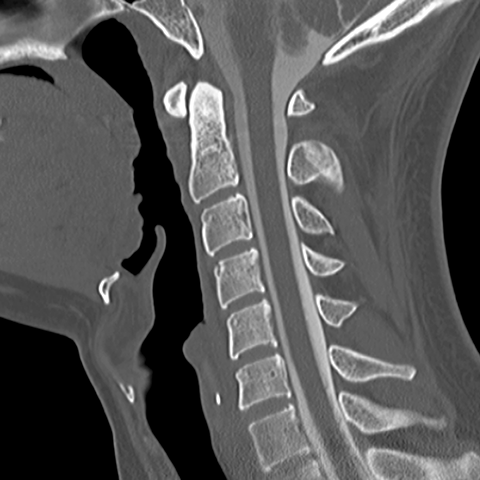

Cervical Spine [7 of 8]